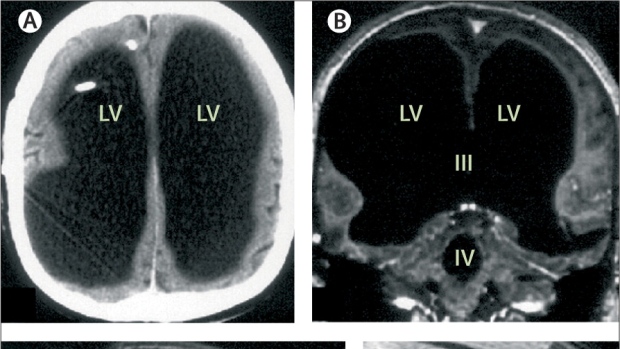

What we think we know about our brains is nothing compared to what we don’t know. This fact is brought into focus by the medical mystery of a 44-year-old French father of two who found out one day that he had most of his brain missing. Instead his skull is mostly full of liquid, with almost no brain tissue left. He has a life-long condition known as hydrocephalus, commonly called “water on the brain” or “water head“. It happens when too much cerebrospinal fluid puts pressure on the brain and the brain’s cavities abnormally increase.

The man continues to live a normal life, being a family man with a wife and kids, while working as a civil servant. All this while having 3 of his main brain cavities filled with only fluid and his brainstem and cerebellum stuck into a small space that they share with a cyst.